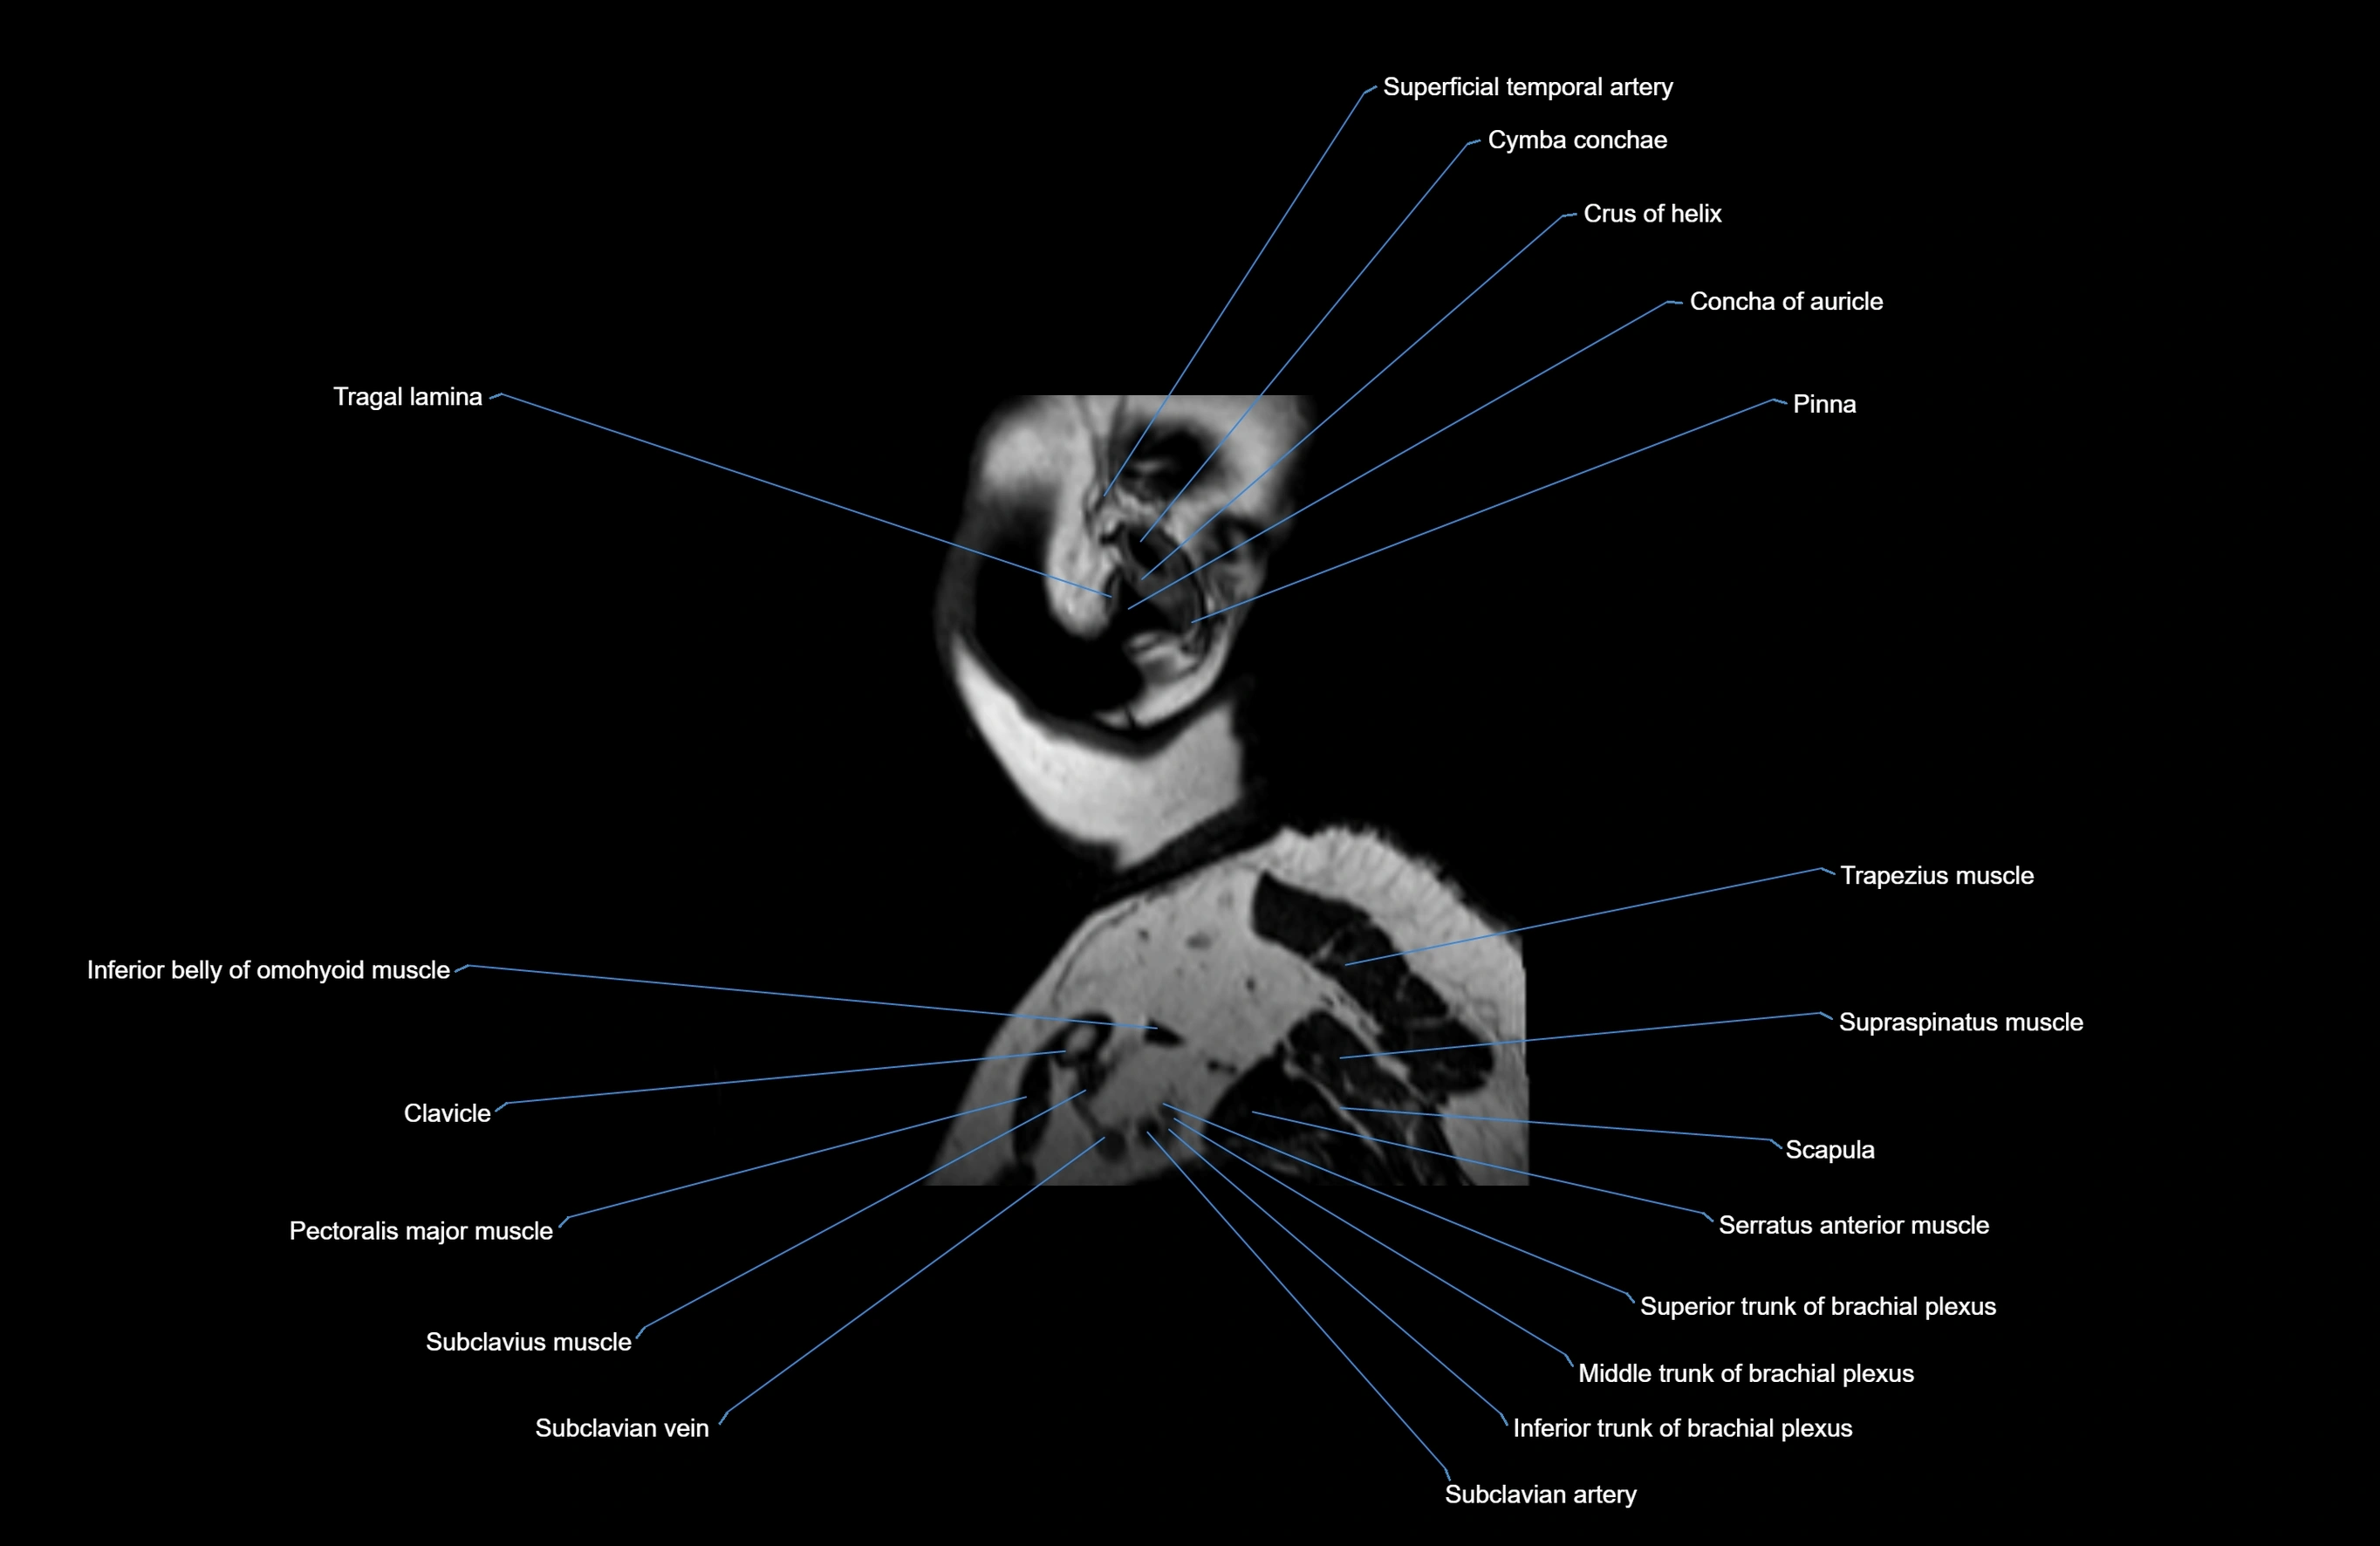

MRI images